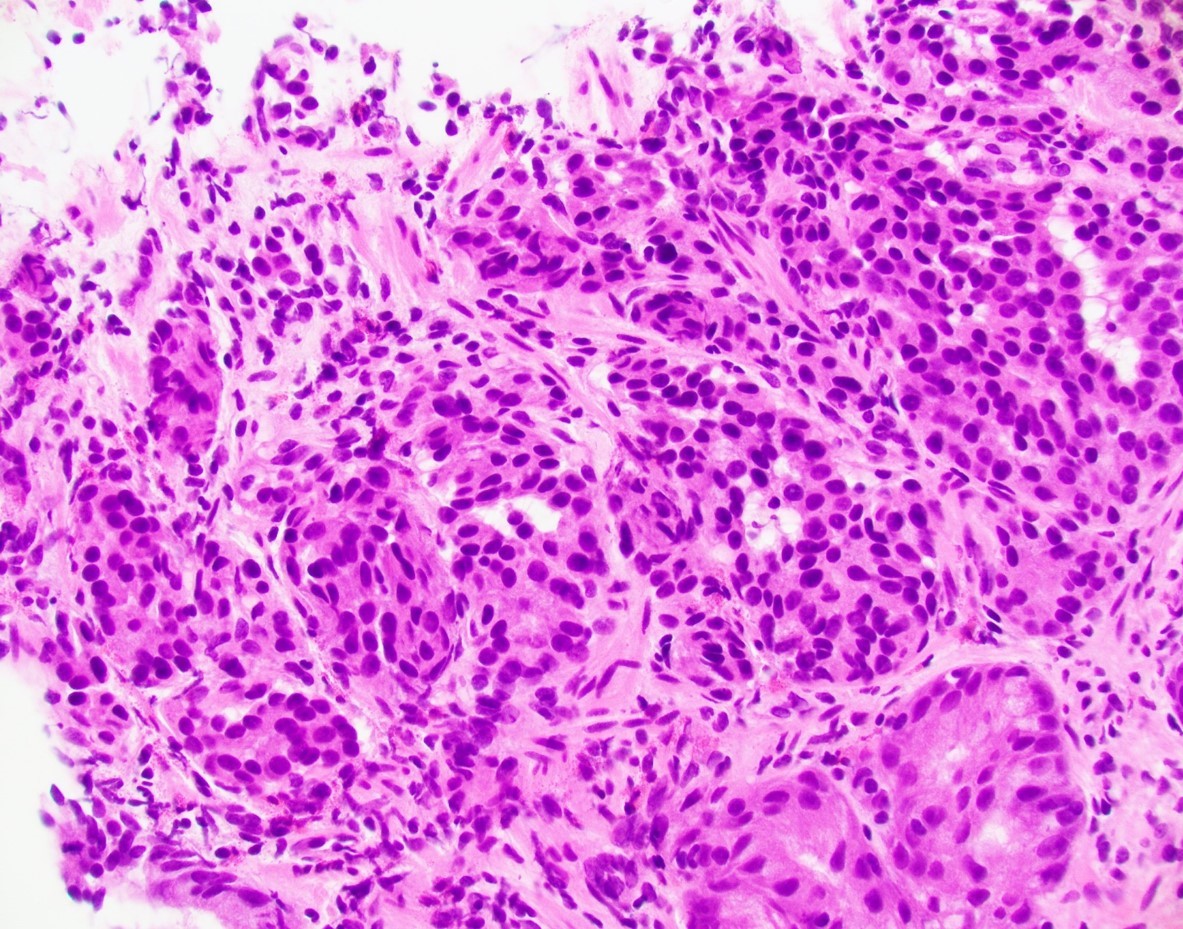

A 56-year-old female underwent upper endoscopy for dyspepsia. A 1 cm gastric nodule was found and biopsied. The histological findings are shown in Figure1 (low power) and Figure 2 (high power). Synaptophysin immunostaining of the tumor (Figure 3) and the background mucosa (Figure 4) are included.

This NET is occurring in a background of atrophic oxyntic mucosa, also known as autoimmune metaplastic atrophic gastritis ( AMAG), which typically shows nodular neuroendocrine cell hyperplasia (ECL) highlighted by synaptophysin stain ( Figure 4}. Intestinal metaplasia is also seen in Figure 1. Psedopyloric metaplasia (another characteristic) feature cannot be appreciated in the provided photographs. Even though Gastrin stain is not provided, the staining pattern of neuroendocrine cells is not that of G cells. Type 1 gastric NETs are typically small, multiple, low grade, associated with antibodies for intrinsic factor/ parietal cell, often have iron deficiency or B12 deficiency, and are managed by endoscopic surveillance. Type 3 NETs are sporadic, not associated with atrophic corpus gastritis. Type 2 are rare, can show ECL hyperplasia, but are associated with MEN1/gastrinoma and parietal cell hyperplasia.